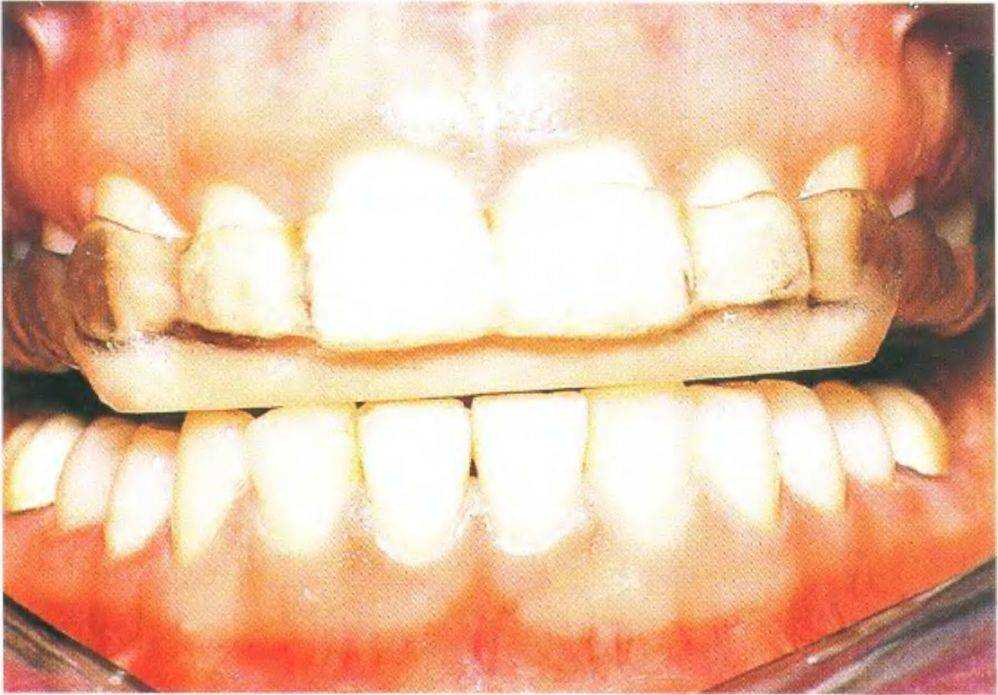

Рис. 3-38с. У пациентки эксцентричный бруксизм

Через две недели пациентка констатировала отсутствие болей. Каппу модифицировали с помощью ФКК для создания передней направляющей. Правильный контур кривизны может быть определен с помощью: 1) анализа небного контура передних зубов (рис. 3-38h); 2) анализа дистального контура боковых зубов (последний определяется с помощью сагиттального распила модели челюсти через вершины опорных бугорков); 3) арифметического и геометрического анализа протрузионных данных аксиографии.

Однако в данном клиническом случае жевательные зубы были настолько плоскими в результате бруксизма, что не позволяли провести анализ контура кривизны. Передние зубы также были стерты до такой степени, что небная кривизна, необходимая для анализа, была слишком короткой для точного определения контура кривизны (рис. 3-38i).